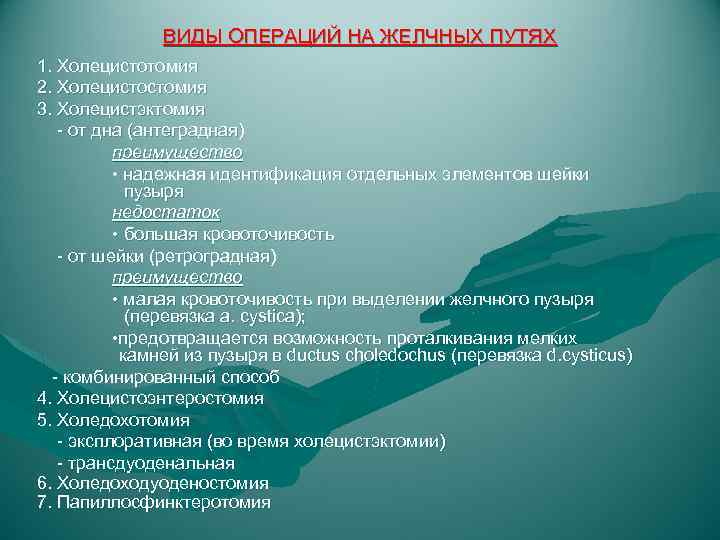

ВИДЫ ОПЕРАЦИЙ НА ЖЕЛЧНЫХ ПУТЯХ 1. Холецистотомия 2. Холецистостомия 3. Холецистэктомия - от дна (антеградная) преимущество • надежная идентификация отдельных элементов шейки пузыря недостаток • большая кровоточивость - от шейки (ретроградная) преимущество • малая кровоточивость при выделении желчного пузыря (перевязка a. cystica); • предотвращается возможность проталкивания мелких камней из пузыря в ductus choledochus (перевязка d. cysticus) - комбинированный способ 4. Холецистоэнтеростомия 5. Холедохотомия - эксплоративная (во время холецистэктомии) - трансдуоденальная 6. Холедоходуоденостомия 7. Папиллосфинктеротомия

ВИДЫ ОПЕРАЦИЙ НА ЖЕЛЧНЫХ ПУТЯХ 1. Холецистотомия 2. Холецистостомия 3. Холецистэктомия - от дна (антеградная) преимущество • надежная идентификация отдельных элементов шейки пузыря недостаток • большая кровоточивость - от шейки (ретроградная) преимущество • малая кровоточивость при выделении желчного пузыря (перевязка a. cystica); • предотвращается возможность проталкивания мелких камней из пузыря в ductus choledochus (перевязка d. cysticus) - комбинированный способ 4. Холецистоэнтеростомия 5. Холедохотомия - эксплоративная (во время холецистэктомии) - трансдуоденальная 6. Холедоходуоденостомия 7. Папиллосфинктеротомия